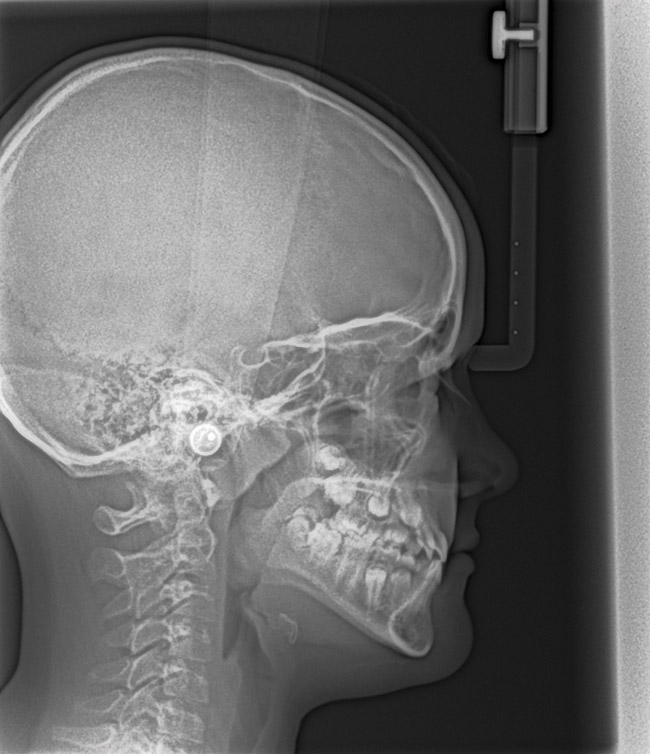

(15.) Cephalometric evaluation demonstrates significant tonsillar blockage of the airway and bimaxillary retursion.

Figure 15

(22.) Radiograph highlights the obstructed nasal airway preoperatively. Three months after T&A, another PSG demonstrated an AHI of 0.3 and RERA of 0.0/hr.

Figure 22